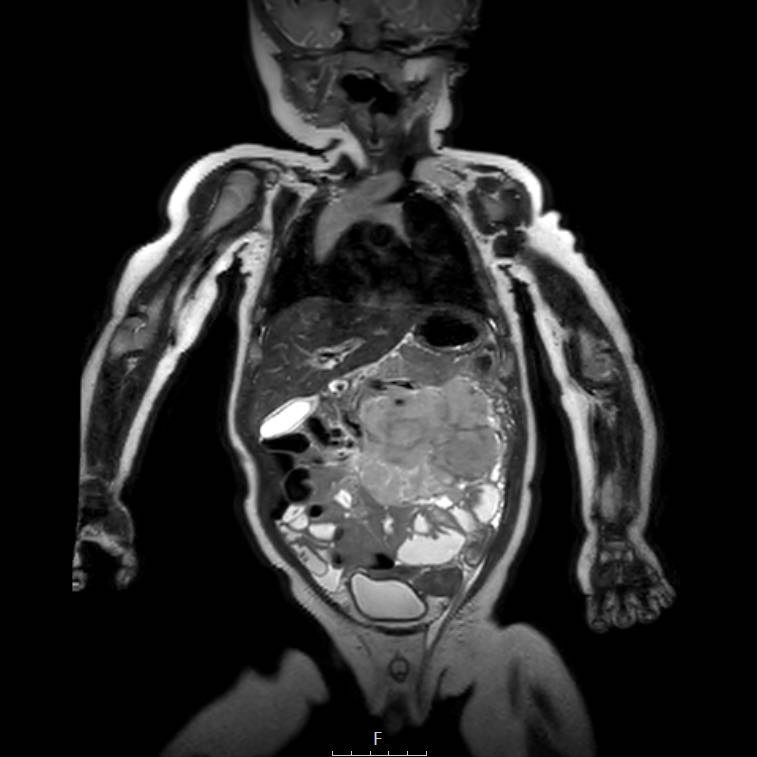

Cuộn qua chuỗi ảnh T2 theo mặt phẳng coronal.

Nghiên cứu các hình ảnh và sau đó tiếp tục đọc.

The findings are:

- Mass with encasement of the aorta and splanchnic vessels.

- Lan rộng dọc theo cột sống ngực nhưng không xâm lấn vào ống sống.

- Small liver metastases.

- Left supraclavicular mass.